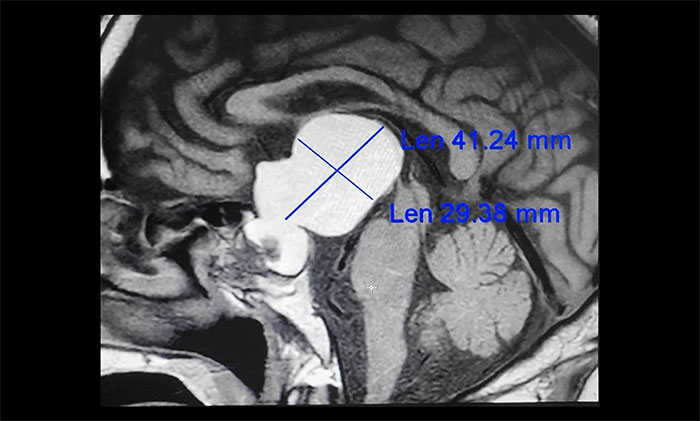

▲ 鞍区囊性占位病变

通过进一步完善头颅磁共振检查,提示患者鞍区囊性占位病变,考虑为颅咽管瘤,瘤体最大直径超过4cm。